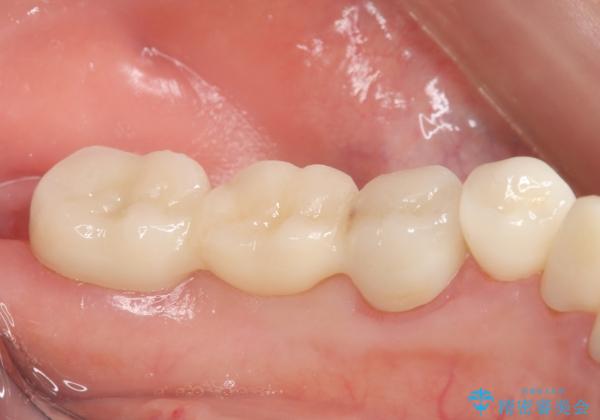

銀歯のブリッジをジルコニアブリッジへ

- 笑った時に大きく見えてしまう奥歯の銀歯ブリッジを白くしたいと希望され来院されました。

強度があり、審美性にも優れるジルコニアブリッジに置き替えていく治療計画としました。

ブリッジに見えない自然な仕上がりに喜んでいただくことができました。